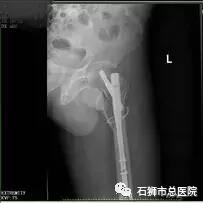

股骨骨折

股骨粗隆间粉碎性骨折

手术 · 后